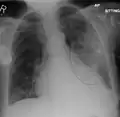

AP CXR showing left lower lobe pneumonia associated with a small left sided pleural effusion -

AP CXR showing right lower lobe pneumonia -

AP CXR showing pneumonia of the lingula of the left lung -